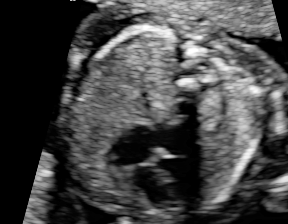

Finally, correctly classified and mis-classified examples of using MIDNet are presented in Fig. 11 (a).

| GT | 4CH | Femur | Lips |

| TP |

\stackunder 4CH |

\stackunder Femur |

\stackunder Lips |

| FP |

\stackunder Abdominal |

\stackunder LVOT |